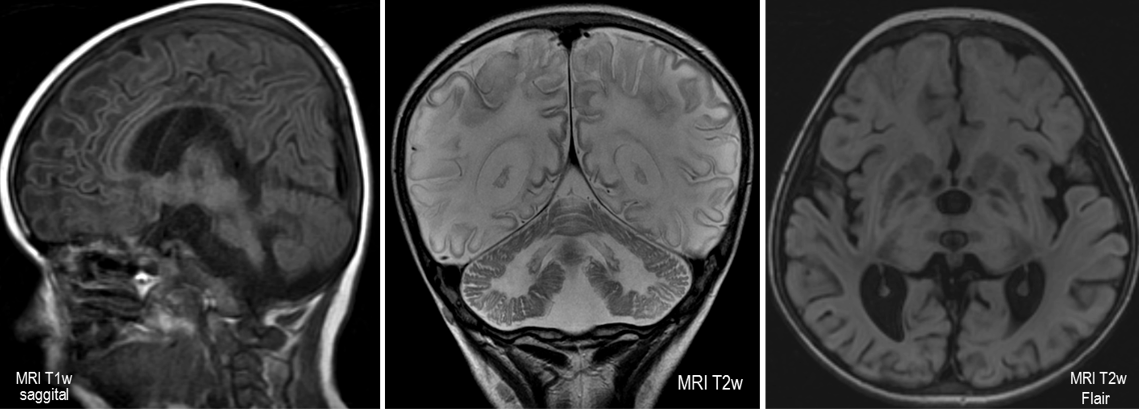

Gangliosidóza čiže Tay-Sachsova choroba, amaurotická familiárna idiocia (duševná zaostalosť), (anglicky Tay-Sachs disease, GM2 gangliosidosis alebo hexosaminidase A deficiency) je veľmi vzácna dedičná metabolická choroba, ktorej príčinou je gén na 15. chromozóme, autozomálne recesívnym typom dedičnosti. Spôsobuje nedostatočnosť enzýmu pri katabolizme (rozklade) špecifických tukov - gangliozidov. Tento tuk sa potom v detských rokoch ukladá v mozgu a bráni funkcii mozgových buniek. Tay-Sachsova choroba je fatálne ochorenie, smrť prichádza väčšinou okolo tretieho roku života. Incidencia je 1: 4000 narodených, zvýšený výskyt je zaznamenaný u aškenázskej židovskej populácie.